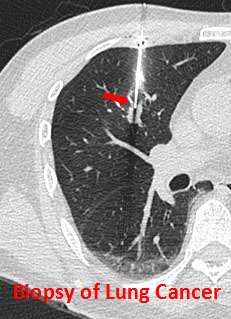

- Biopsy of the lung